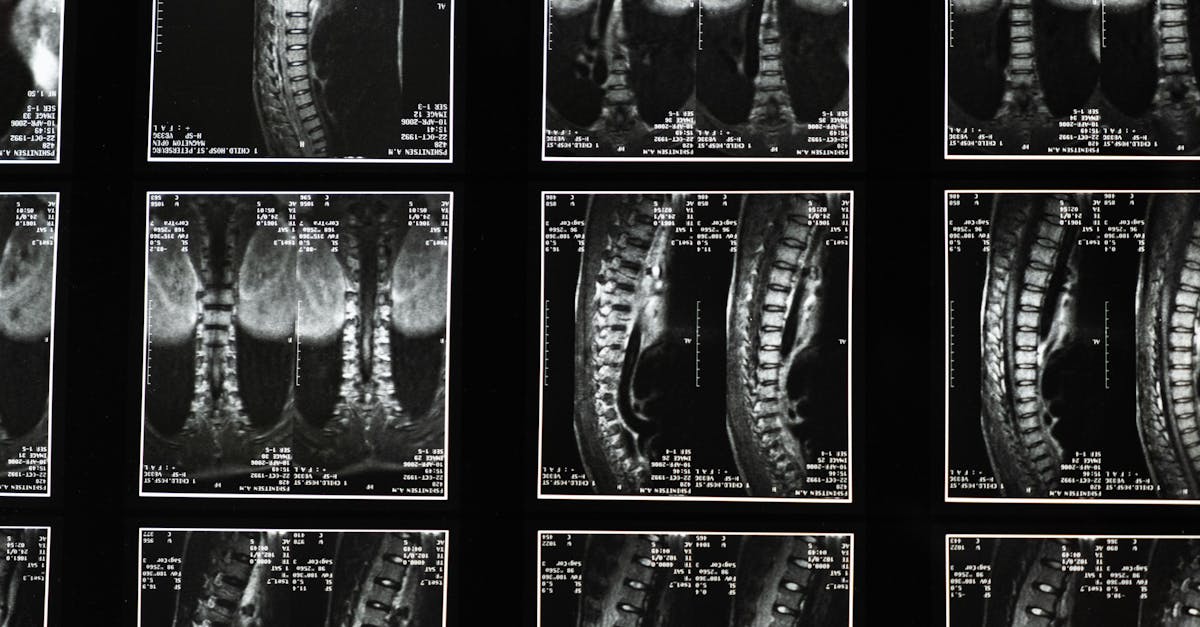

Une séance de décompression neurovertébrale se déroule généralement en plusieurs étapes. Tout d’abord, un diagnostic précis est établi, basé sur des évaluations cliniques et éventuellement des imageries médicales. Le professionnel détermine alors le plan de traitement adapté aux besoins du patient.

Les bombements discaux se produisent lorsque le matériau gélatineux à l’intérieur des disques intervertébraux se déplace, provoquant une dilatation de la paroi externe du disque. Ce phénomène peut entraîner des douleurs chroniques, de la raideur et une réduction de la mobilité. La décompression neurovertébrale utilise des appareils spécialisés pour appliquer une force de traction contrôlée sur la colonne vertébrale, créant ainsi un espace entre les vertèbres. Ce procédé aide à détendre les muscles tendus et à favoriser la circulation sanguine dans la région, ce qui est crucial pour la guérison.